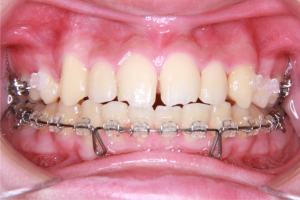

※矯正治療中の正面

上記の写真のように、ハーフリンガル矯正では、上の歯は内側に装置を装着するため、見た目には装置が付いていないように見えることがあります。

※矯正治療が進んだ際の口元の拡大写真

上の前歯2本の形にバランスの乱れがあるため、この時点ではまだ歯と歯の間にすき間が残っている状態です。